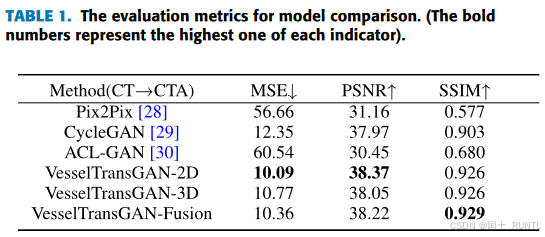

对比了Pix2Pix、CycleGAN和ACL-GAN3种方法,评价指标有MSE、PSNR和SSIM,对比结果如下图所示: